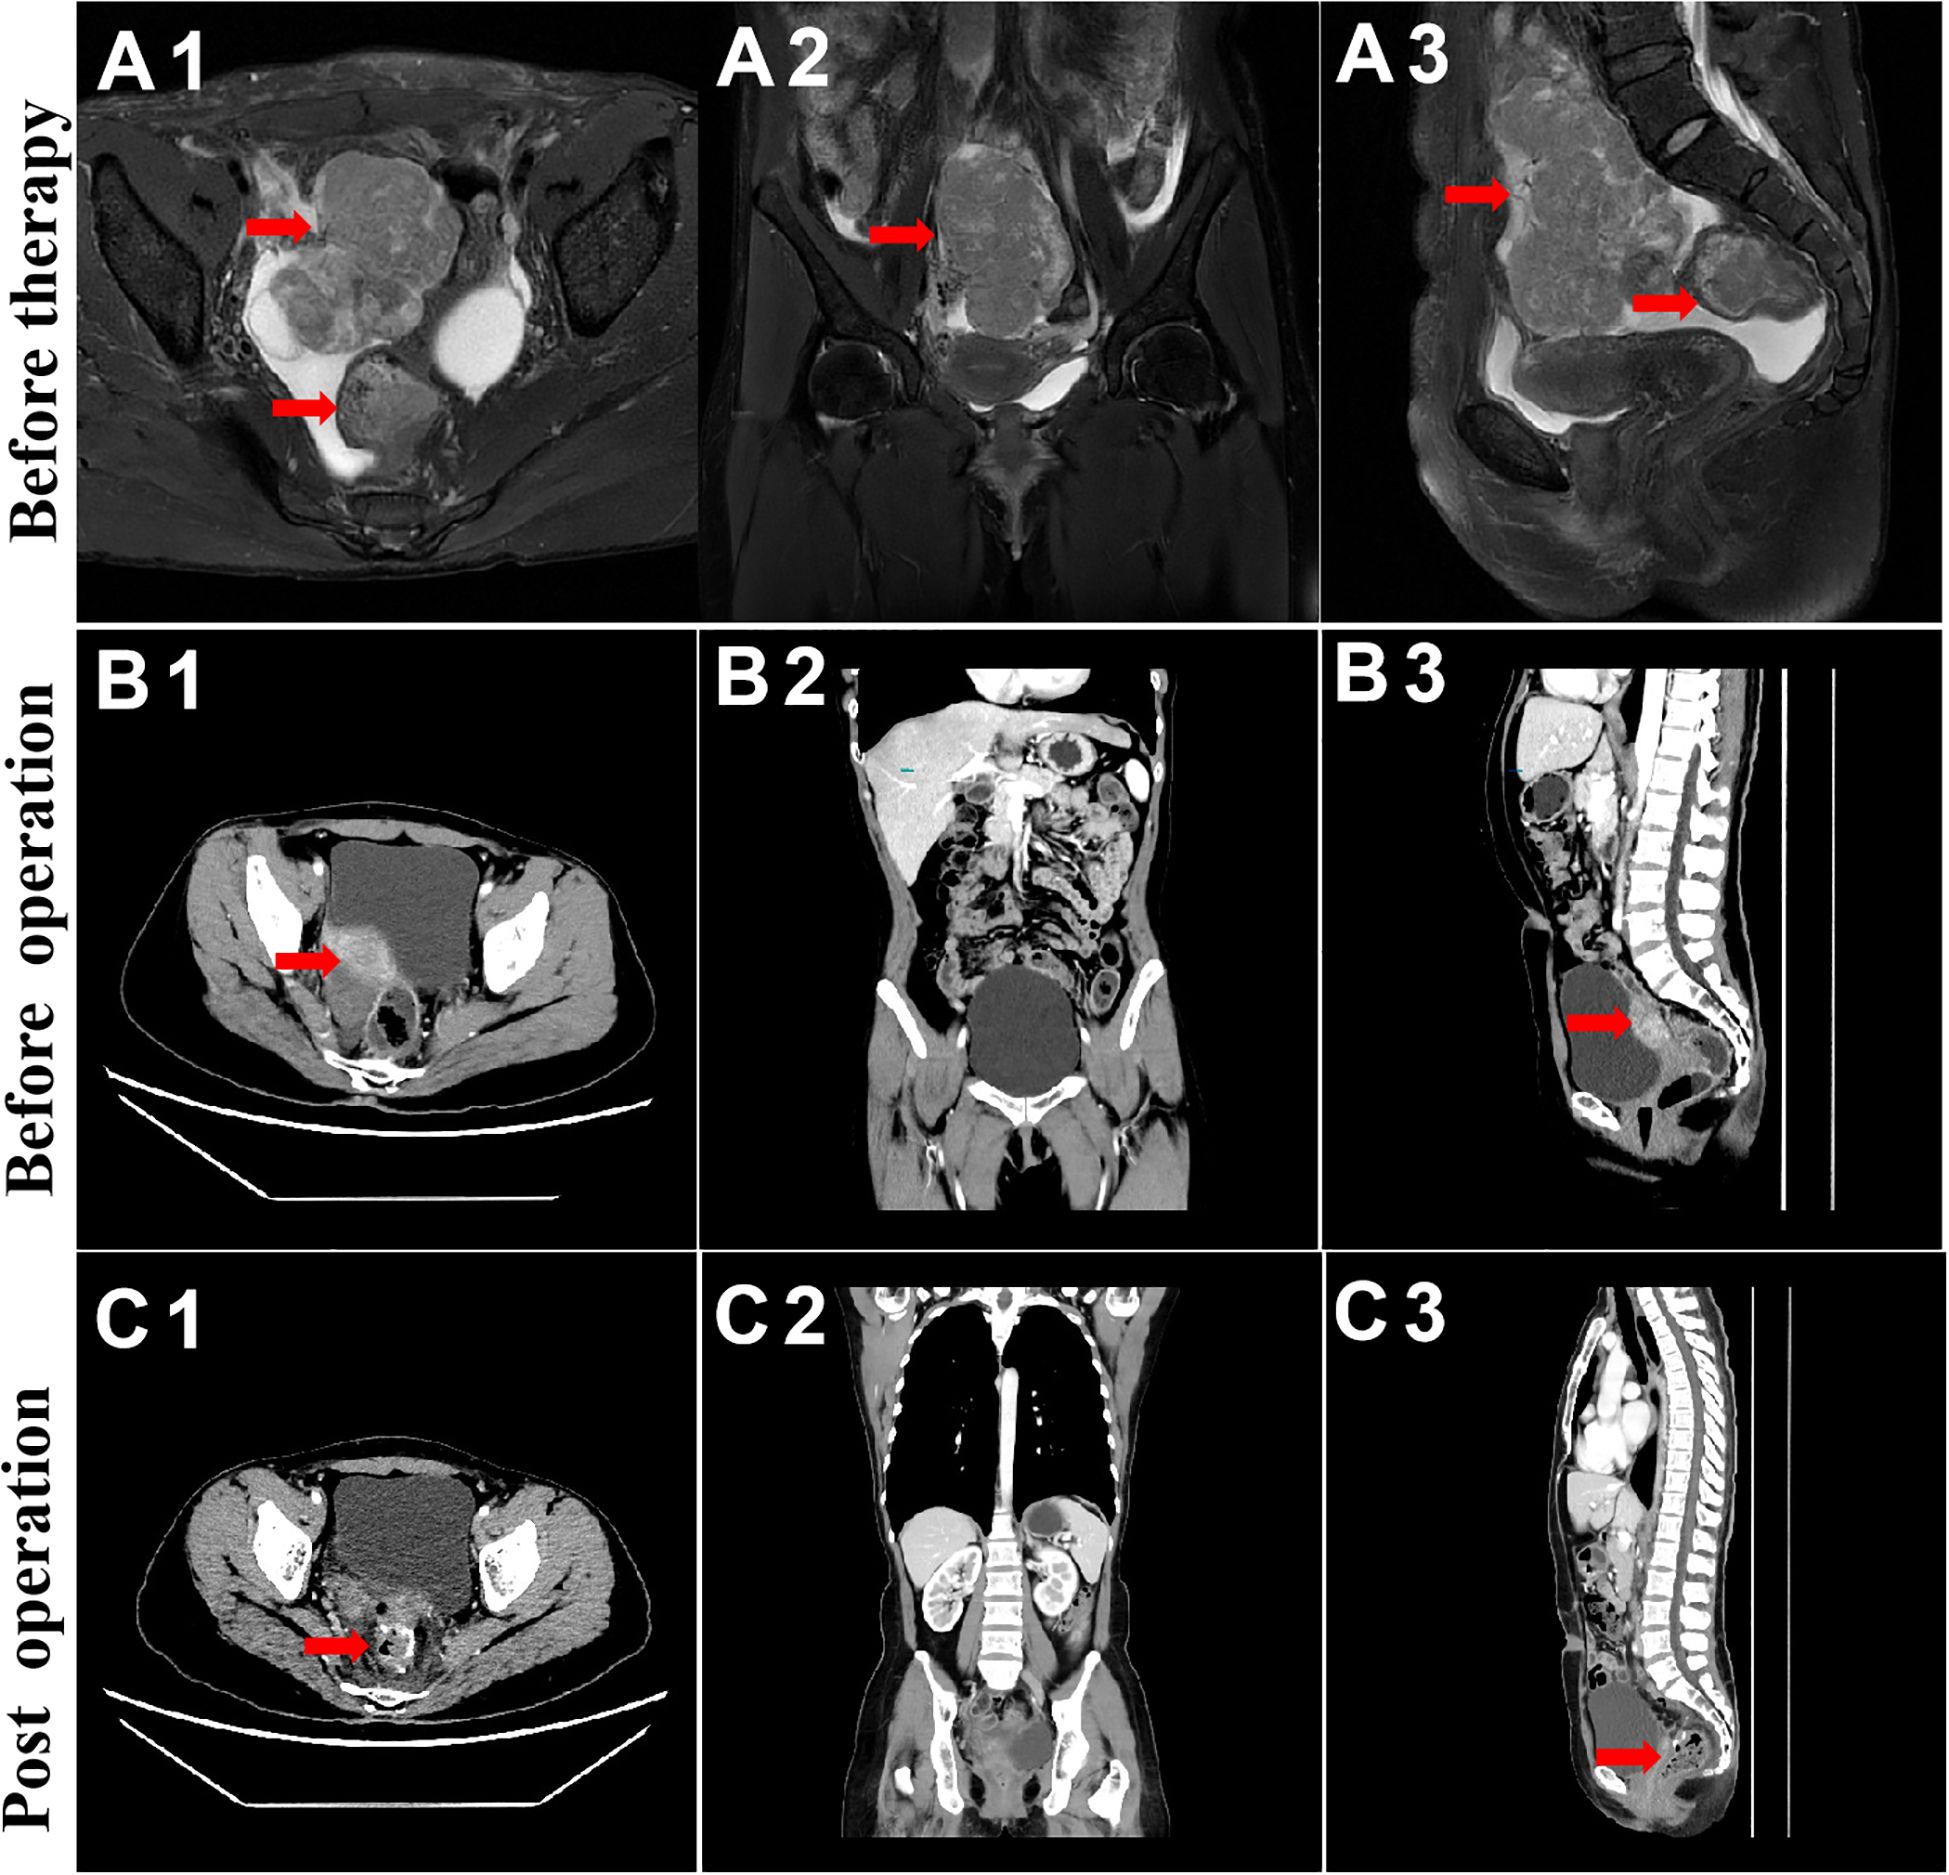

On 2nd June, 2022, chest and abdominal enhancement CT was repeated, which suggested the presence of a mass on the basis of an abnormal single shadow on the right margin of the uterus. The mass measured ~37 mm × 26mm, which was significantly reduced compared with the findings of the previous CT scan. Additionally, there was a significantly reduced thickening of the upper rectal intestinal wall (Figure 2), which was previously thicker by about 8mm and involved an area of about 25mm. A rounded low-density nodule measuring ~14 mm × 11mm was seen in liver S5. Lymph node shadow was seen next to the abdominal aorta, which had a diameter of about 8mm and was significantly reduced compared with the previous CT findings.

Figure 2

MRI and CT scan images showing a pelvic mass in different stages of treatment. The top row (A1, A2, A3) shows images before therapy with the mass prominently highlighted by red arrows. The middle row (B1, B2, B3) features images before operation, showing the mass marked by arrows. The bottom row (C1, C2, C3) displays post-operation images where the mass is reduced or absent, as indicated by arrows. Each column represents a different plane of view: axial, coronal, and sagittal.

Figure 2. MRI and CT evaluation of ovarian and rectal tumors. From top to bottom, before chemotherapy and immunotherapy (A), before surgical treatment (B), and during 3-week postoperative follow-up (C).